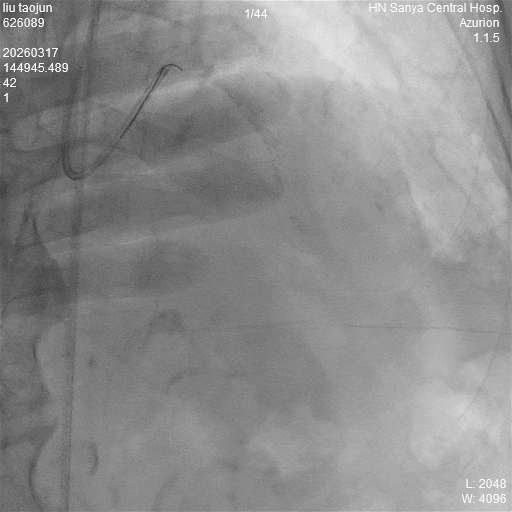

▲术后